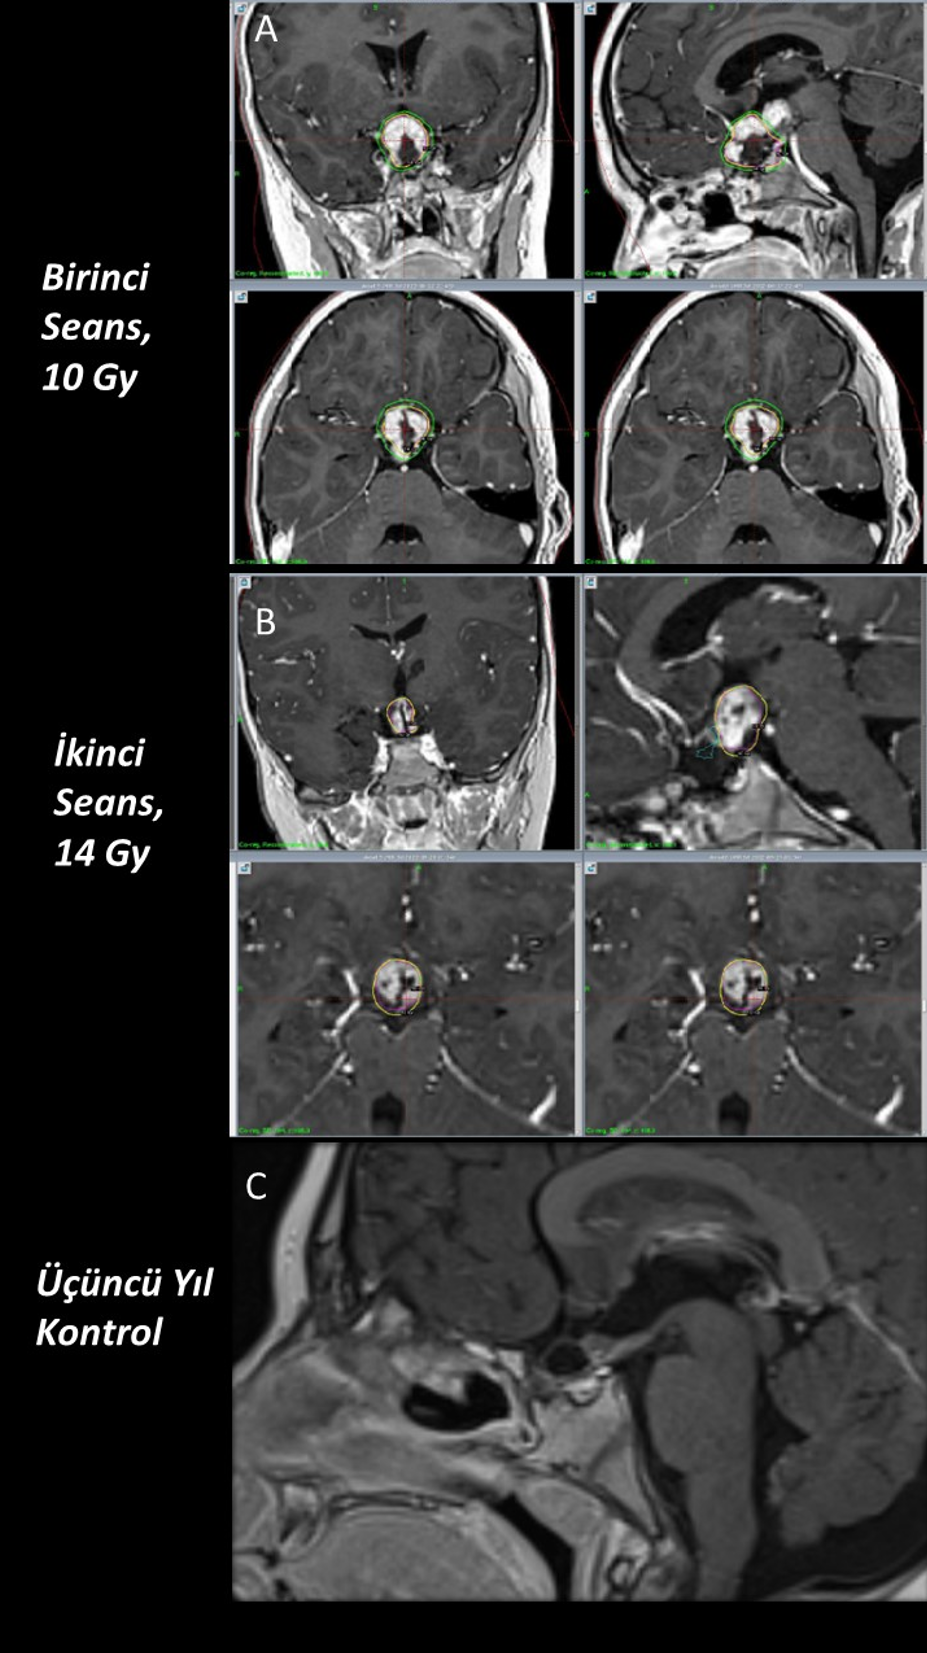

Hacmi büyük ve kritik anatomik yapılara komşu lezyonlarda, radyasyon güvenliğini artırmak amacıyla hacimsel evreleme (volume staging) yaklaşımı tercih edilmiştir. Bu yöntemde hedef hacim alt bölümlere ayrılarak farklı seanslarda tedavi uygulanmış ve her seans stereotaktik çerçeve ile yeniden planlanarak gerçekleştirilmiştir.

Patolojik tanılara göre değerlendirildiğinde en sık karşılaşılan tümör grubu gliyal tümörler olup, dört hastada saptanmıştır. Bu hastaların ilki 15 yaşındaki kız hasta patoloji sonucu DSÖ derece 3 gliyal kitle olarak raporlanmıştır. Cerrahi sonrası dönemde rezidü kitlesine yönelik lezyon için Karnofsky skoru düşük olması nedeniyle radyoterapi (RT) uygun görülmedi ve hastaya GKRC yapıldı. 5. ay kontrol görüntülemesinde lezyon boyutlarında artış olması ve Karnofsky skoru düzelen hastaya RT yapıldı. Hasta RT’den 2 ay sonra vefat etti. İkinci hasta 15 yaş kız hasta olup patolojisi yüksek dereceli gliyal kitle olarak sonuçlanmış. Karnofsky skoru düşük olduğu için hastaya RT yapılamadı ve GKRC planlandı. 7. ay kontrol görüntülemesinde progresyon izlenen hastanın Karnofsky skor düşüklüğü olması nedeniyle RT planlanmadı ve tekrar GKRC uygulandı. Hasta ilk GKRC tedavisinin 8. ayında vefat etti (Şekil 2). Diğer iki olgudan biri olan 17 yaşındaki kız hastada beyin sapı yerleşimli pilositik astrositoma (DSÖ Derece 1) yönelik hacim bölünerek 18 aylık süreçte 5 farklı seansta ve her tedavide stereotaktik çerçeve yeniden uygulanarak GKRC gerçekleştirildi. 96 ay sonunda lezyonda küçülme izlendi. Bu olguda lezyonun hacmi ve beyin sapı yerleşimi nedeniyle kritik nörovasküler yapılara yakınlığı göz önünde bulundurularak hacimsel evreleme uygulanmış, hedef hacim alt bölümlere ayrılarak farklı marjinal dozlar her bir alt hacme ayrı ayrı planlanmış ve belirli zaman aralıklarıyla uygulanmıştır. 11 yaşındaki erkek hastada ise tektal yerleşimli Diffüz Astrositomun (DSÖ Derece 2) tedavi sonrasındaki 96 aylık takibinde stabil seyrettiği görüldü. Patolojilere göre marjinal doz, takip süreleri ve sonuçlar Tablo 1’de özetlenmiştir.

Kraniofarengiom tanılı iki erkek hastadan ilki 7 yaşında olup cerrahi patolojisi adamantinamatöz kraniofarengiom olarak sonuçlanmıştır. Önce transkraniyal, 4 ay sonra transsfenoidal yolla cerrahi yapılan hastaya ilk ameliyatının 6. ayında rezidü kitle nedeniyle GKRC uygulandı. 9. ayında kitlenin kistik komponenti için cerrahi yapılan hastanın 12 aylık takibi sonucunda kitlenin kaybolduğu görüldü. Diğeri hasta ise 6 yaşında olup transsfenoidal yolla 2 kez ameliyat edilmiş ve rezidü kitlesine yönelik hacim bölünerek 2 seans GKRC yapıldı (Şekil 4). 37 aylık takipte kitlenin kaybolduğu tespit edilmiştir.